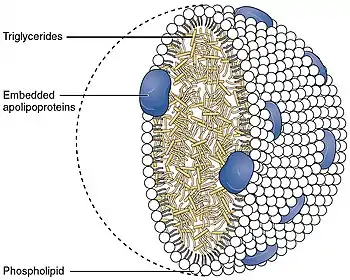

The low-density lipoprotein receptor (LDL-R) is a mosaic protein of 839 amino acids (after removal of 21-amino acid signal peptide)[5] that mediates the endocytosis of cholesterol-rich low-density lipoprotein (LDL). It is a cell-surface receptor that recognizes apolipoprotein B100 (ApoB100), which is embedded in the outer phospholipid layer of very low-density lipoprotein (VLDL), their remnants—i.e. intermediate-density lipoprotein (IDL), and LDL particles. The receptor also recognizes apolipoprotein E (ApoE) which is found in chylomicron remnants and IDL. In humans, the LDL receptor protein is encoded by the LDLR gene on chromosome 19.[6][7][8] It belongs to the low density lipoprotein receptor gene family.[9] It is most significantly expressed in bronchial epithelial cells and adrenal gland and cortex tissue.[10]

LDL receptor mediates the endocytosis of cholesterol-rich LDL and thus maintains the plasma level of LDL.[20] This occurs in all nucleated cells, but mainly in the liver which removes ~70% of LDL from the circulation. LDL receptors are clustered in clathrin-coated pits, and coated pits pinch off from the surface to form coated endocytic vesicles that carry LDL into the cell.[21] After internalization, the receptors dissociate from their ligands when they are exposed to lower pH in endosomes. After dissociation, the receptor folds back on itself to obtain a closed conformation and recycles to the cell surface.[22] The rapid recycling of LDL receptors provides an efficient mechanism for delivery of cholesterol to cells.[23][24] It was also reported that by association with lipoprotein in the blood, viruses such as hepatitis C virus, Flaviviridae viruses and bovine viral diarrheal virus could enter cells indirectly via LDLR-mediated endocytosis.[25] LDLR has been identified as the primary mode of entry for the Vesicular stomatitis virus in mice and humans.[26] In addition, LDLR modulation is associated with early atherosclerosis-related lymphatic dysfunction.[27] Synthesis of receptors in the cell is regulated by the level of free intracellular cholesterol; if it is in excess for the needs of the cell then the transcription of the receptor gene will be inhibited.[28] LDL receptors are translated by ribosomes on the endoplasmic reticulum and are modified by the Golgi apparatus before travelling in vesicles to the cell surface.